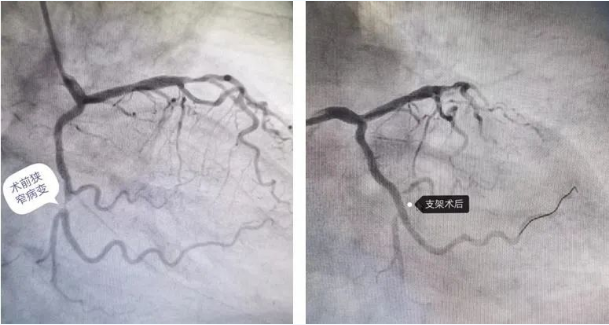

前几天,80岁的徐老先生夜间休息时突然出现左侧胸痛症状,呈闷痛,向后背部放射痛,伴有出汗、左上肢麻木等不适,家人急忙将老人送到河北省第八人民医院(河北省老年病医院)心内二科就诊,经检查明确诊断为急性心肌梗死,紧急行冠脉介入治疗。冠状动脉造影术检查显示回旋支近段可见散在斑块,中段可见局限性狭窄,狭窄最重约99%,远端未见明显狭窄,左主干、前降支及右冠未见明显狭窄,经评估后,顺利为老人行经皮冠状动脉支架植入术。

术前、术后病变血管变化

由于救治及时,术后徐老先生胸痛症状消失,两日后可自主活动,日常生活自理。